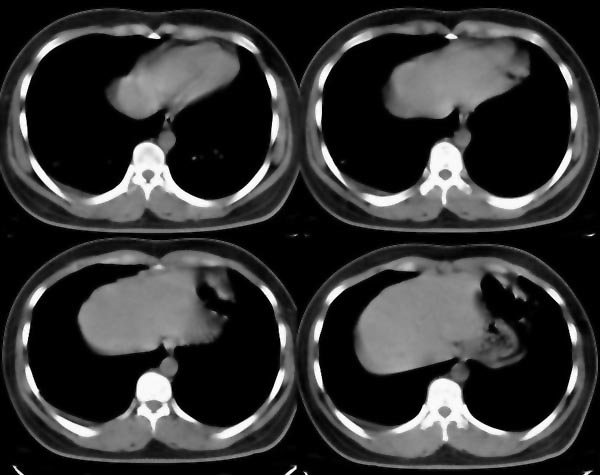

m21y既往体健,否认结核、支扩等病史;1周前患上感,无明显咳嗽,自觉无明显不适。单位体检透视时发现右侧液气胸!cr及ct如下(肺组织窗:l:-598hu w:1132hu):请大家会诊!!

右侧巨大含气囊性病变,壁薄、光整、其外侧见气体。右肺压迫性肺不张、胸腔内见少量积液。纵隔向左侧移位。左肺未见异常。诊断:1.右侧含气肺囊肿(先天性)。2.右侧液气胸。(少量液体)3.右肺压迫性肺不张。我也遇见一例这样的病人。女性。股骨外伤就诊。常规胸片发现右侧囊性病变。